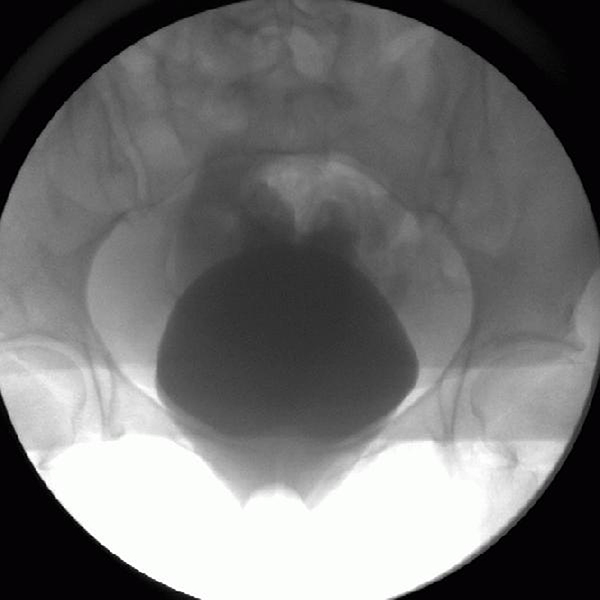

A 40-year-old woman has urine draining from a port site three days following laparoscopic assisted vaginal hysterectomy. Cystogram is shown and bilateral retrograde pyelograms are normal. The next step is:

3

This patient has a large intraperitoneal bladder perforation and urinary ascites from an unrecognized bladder injury during hysterectomy. The best choice for management is immediate transperitoneal exploration with repair of the bladder injury. This will allow drainage of the urinary ascites, washing out of the peritoneal cavity, and significantly reduce the risk of peritonitis and vesicovaginal fistula formation. The use of a pedicalized omental flap to place between the bladder repair and the vaginal cuff suture lines should also be attempted to avoid overlapping suture lines and further minimize risk of post-operative fistula. Prolonged catheter drainage is the incorrect management of an intraperitoneal bladder injury and may result in prolonged urinary ascites with resultant persistent ileus and peritonitis. Bilateral nephrostomy tubes often do not result in complete 12 and would likely result in a prolonged clinical course and delay recovery. Transvaginal repair is the wrong approach to repair an intraperitoneal bladder injury.